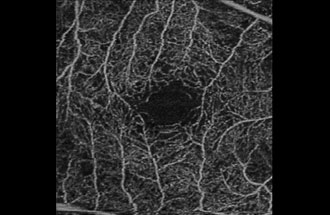

● 光干渉断層血管撮影機器(OCTA)

網膜疾患や緑内障の診断に用いられてきた光干渉断層計(OCT:optical coherence tomography)は、非侵襲的に網膜の断面を描出する機器でとして広く普及しています。当院では、8年前からOCTを導入し、網膜疾患と緑内障の診断と治療に活用してきました。

今回、新たにOCTに血管撮影の機能が付いた光干渉断層血管撮影機器(OCTA: OCT angiography、アンギオOCT)を導入いたしました。

これまで、網膜の血管を描出するには造影剤が必要でした。しかし、この最新の機器を用いることにより、網膜やその下にある脈絡膜血管を、造影剤を用いずに短時間で血管撮影できるようになりました。造影剤を用いた検査(蛍光眼底撮影)は、手間のかかる検査であるだけではなく、副作用のリスクもあるため、実施できない患者様もおられました。 OCTAは、これまでの造影剤を用いた検査の問題点を解決してくれる画期的な機器です。

OCTAを用いることで、これまでの網膜の断層撮影に加えて

② 糖尿病網膜症の早期診断と進展の評価

![]() |

| 糖尿病のない患者さんの 正常眼底 |

糖尿病患者で網膜症なしと 診断された方 |

単純網膜症 |

糖尿病患者さんでは眼底検査で所見がみられない時期にすでに血管の閉塞が始まっていることがわかります。このようにOCTAを用いることで糖尿病網膜症を早期にとらえることが可能です。